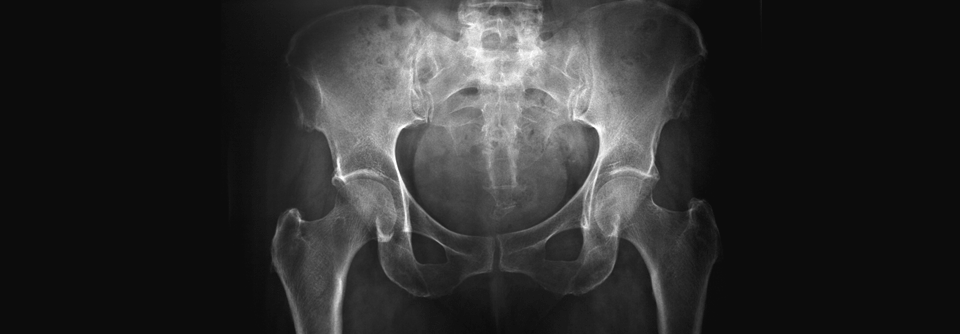

Beim Rückenschmerz hilft die Bildgebung nicht weiter. Beim Rückenschmerz hilft die Bildgebung nicht weiter. © iStock/Filip_Krstic

Beim unspezifischen Rückenschmerz hilft die Bildgebung meist kaum weiter. Die üblichen Verschleißerscheinungen im Lendenwirbelbereich, die bei vielen Patienten gefunden werden, haben für die Therapie nur wenig Bedeutung.